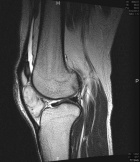

Patient is a 45 y/o Ortho nurse who presented w/ enlarging painful R. knee mass for past year; PMH: ovarian cysts s/p rupture

PE: R. knee w/ well circumscribed mass at the lat. aspect of the patella; + tenderness to palpation; normal PROM; NVI

Zoom image: Radiological image Radiological image.